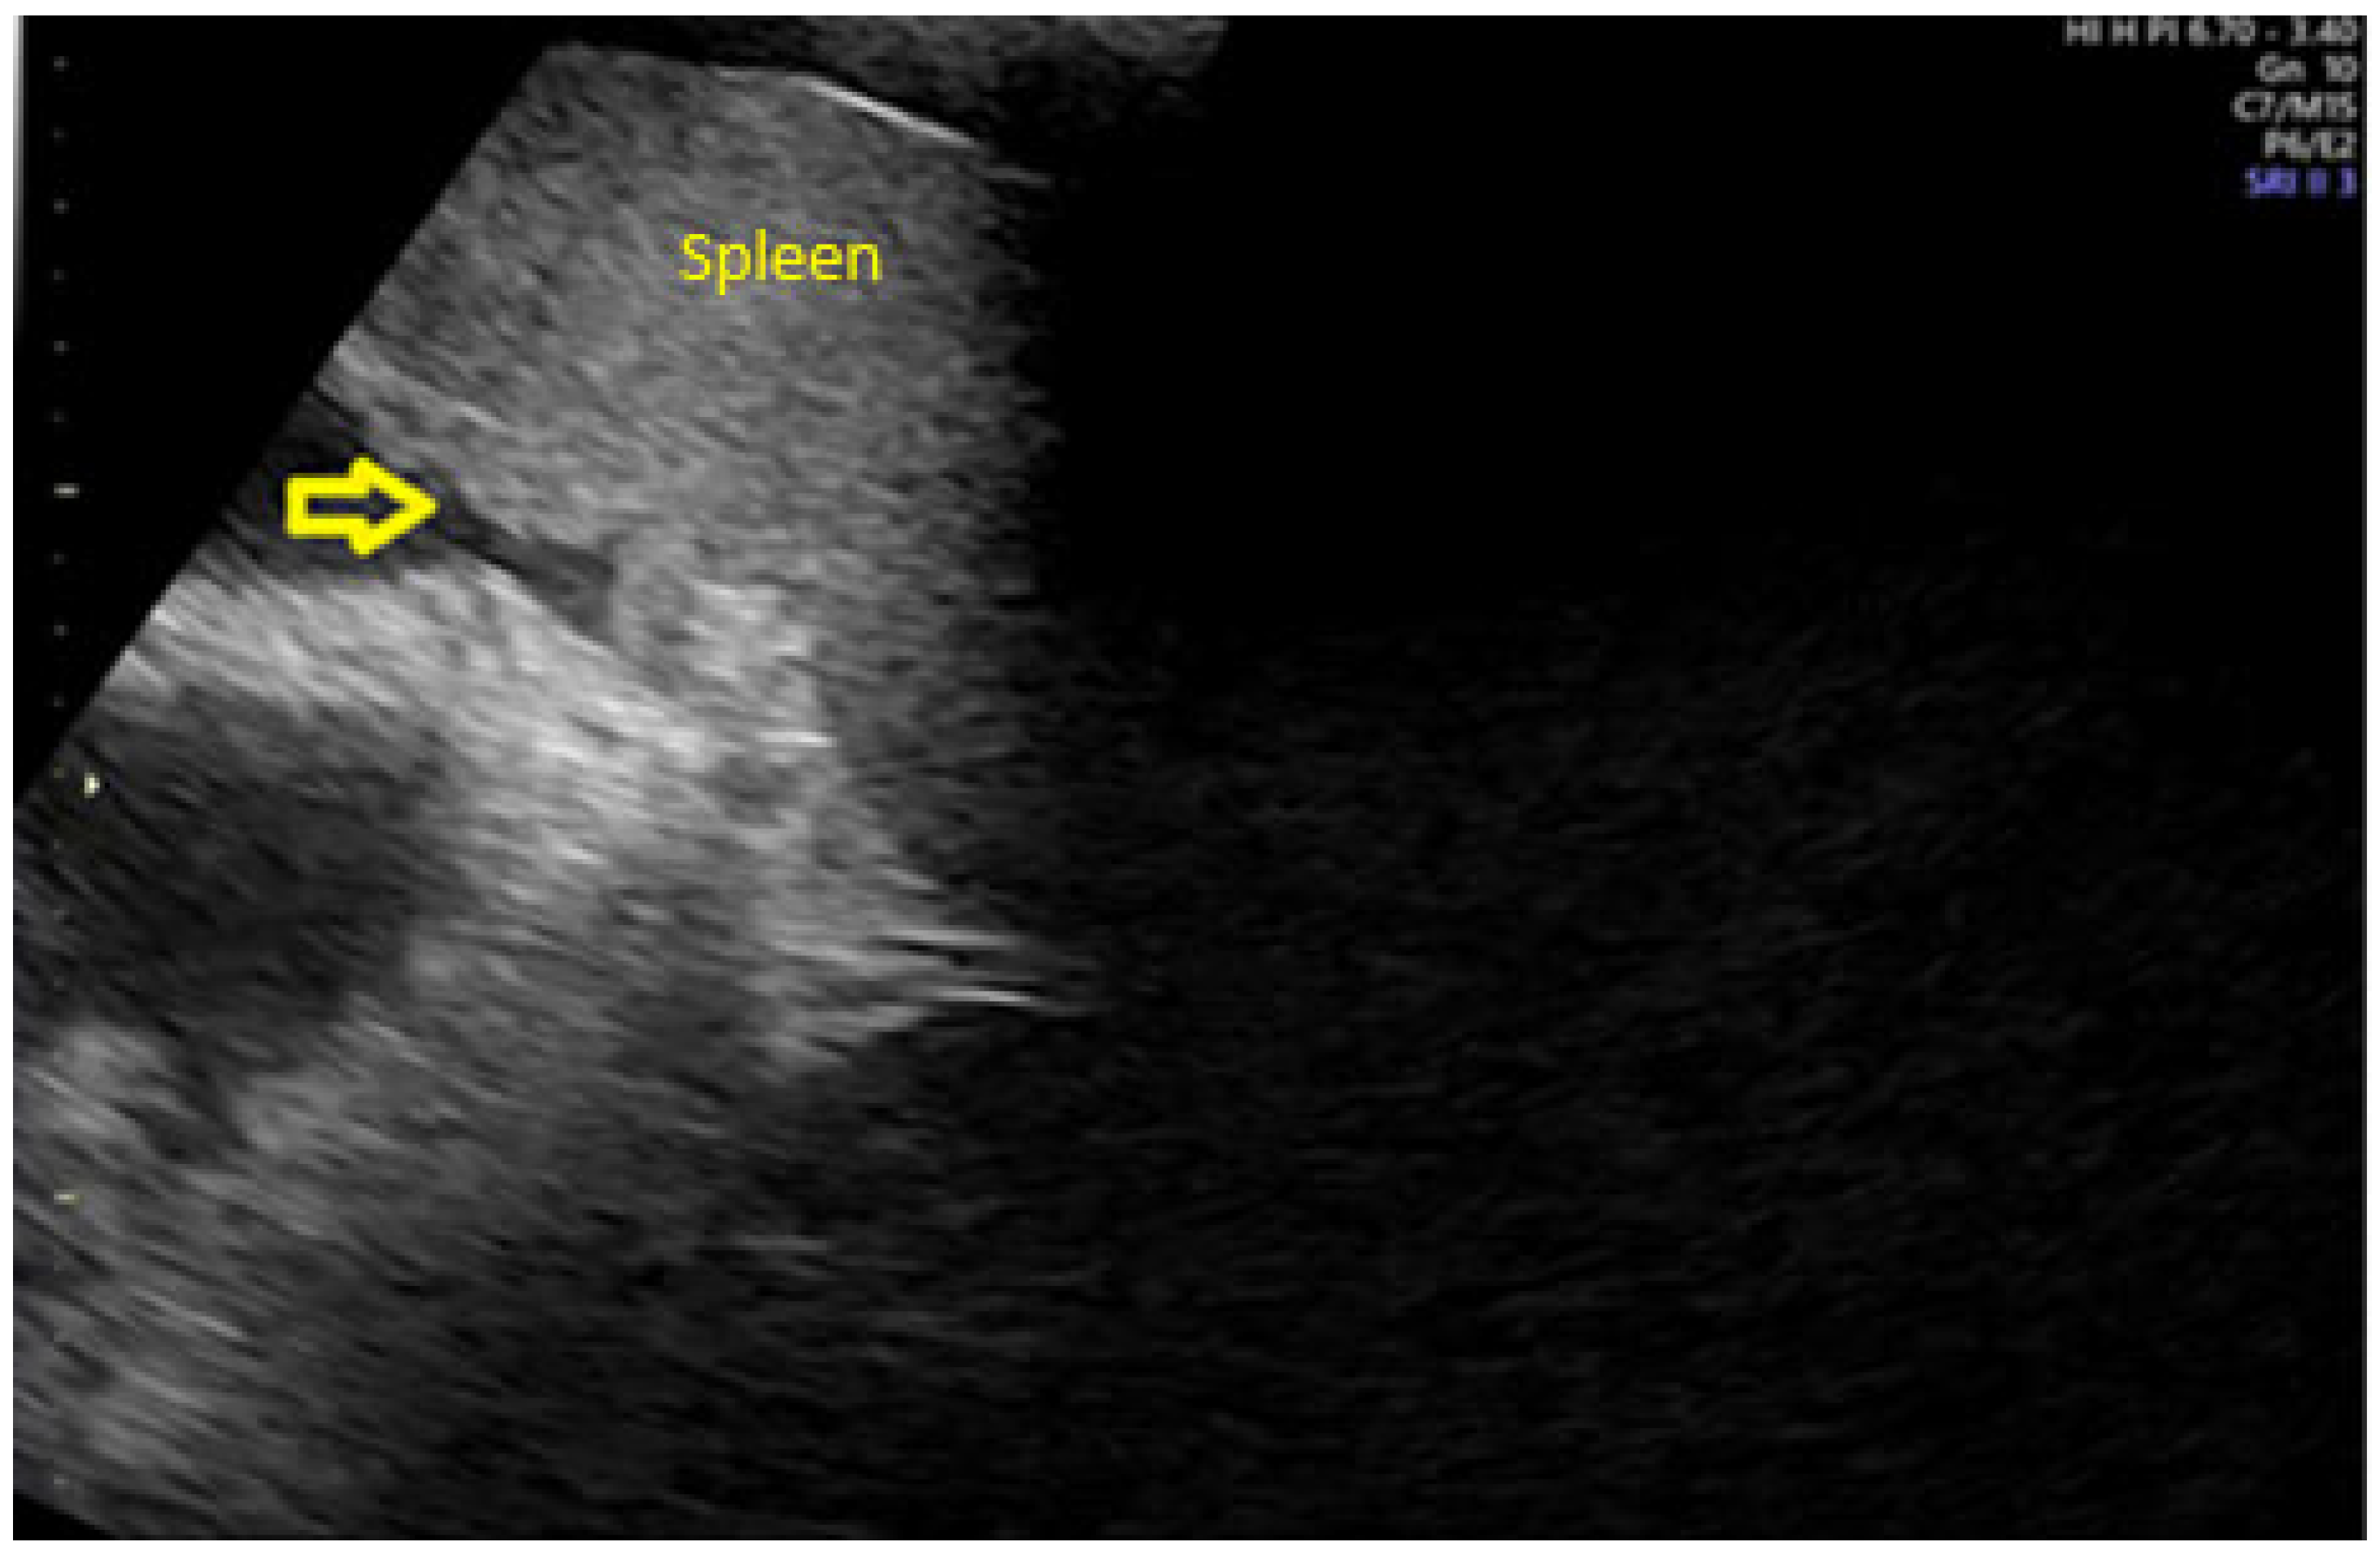

- Savelli, L.; De Iaco, P.; Ceccaroni, M.; Ghi, T.; Ceccarini, M.; Seracchioli, R.; Cacciatore, B. Transvaginal sonographic features of peritoneal carcinomatosis. Ultrasound Obstet. Gynecol. 2005, 26, 552–557. [Google Scholar] [CrossRef]

- Weinberger, V.; Fischerova, D.; Semeradova, I.; Slama, J.; Dundr, P.; Dusek, L.; Cibula, D.; Zikan, M. Prospective Evaluation of Ultrasound Accuracy in the Detection of Pelvic Carcinomatosis in Patients with Ovarian Cancer. Ultrasound Med. Biol. 2016, 42, 2196–2202. [Google Scholar] [CrossRef]

- Fischerova, D.; Zikan, M.; Semeradova, I.; Slama, J.; Kocian, R.; Dundr, P.; Nemejcova, K.; Burgetova, A.; Dusek, L.; Cibula, D. Ultrasound in preoperative assessment of pelvic and abdominal spread in patients with ovarian cancer: A prospective study. Ultrasound Obstet. Gynecol. 2017, 49, 263–274. [Google Scholar] [CrossRef]